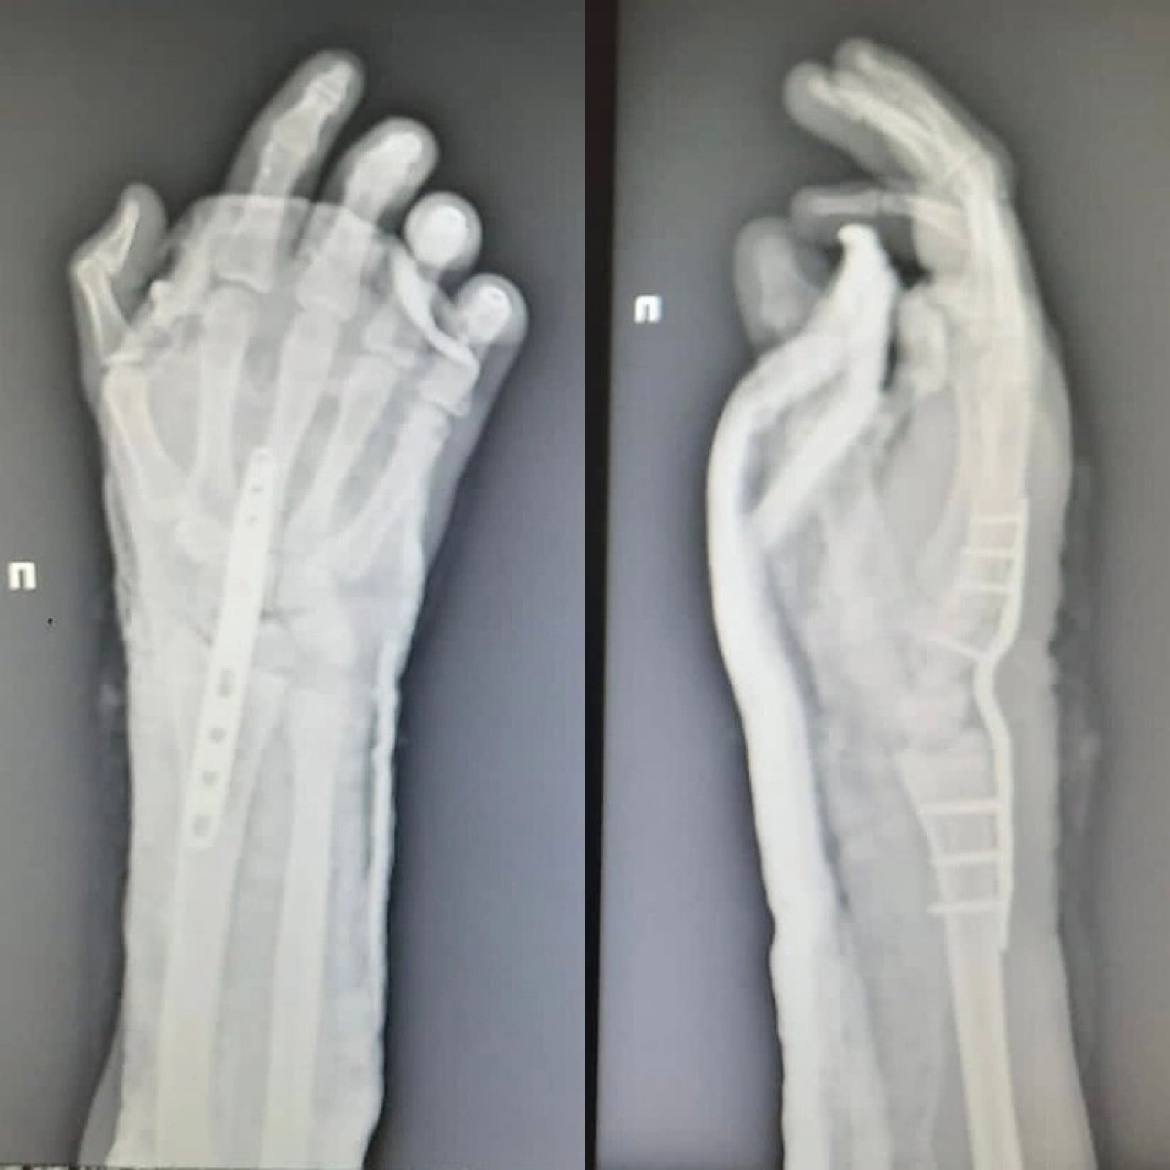

Нижегородские врачи помогли подростку, который отрубил себе кисть руки при колке дров.

Медики провели 16-летнему пациенту операцию по реимплантации конечности. Сейчас его состояние стабильно, кровоснабжение кисти восстановлено. Парню понадобится еще несколько операций, чтобы восстановить функциональность кисти.